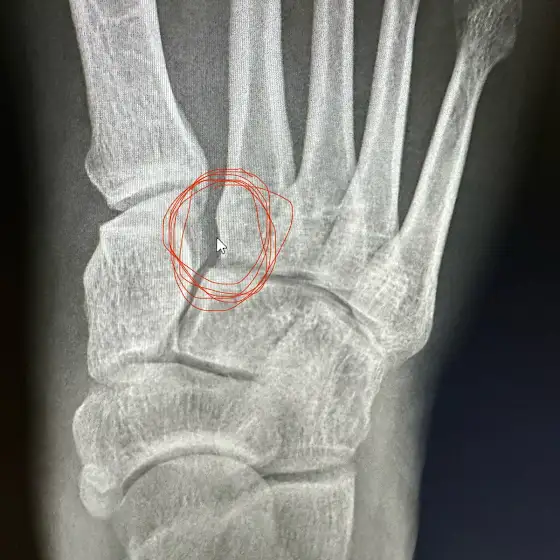

Thanks everyone so much for the support with my surgery. Knowing you’re all there with me makes a huge difference.

The surgery went well. I have a small metal plate reconnecting my lisfranc ligament. Now to manage the pain and heal up. Much love 💕